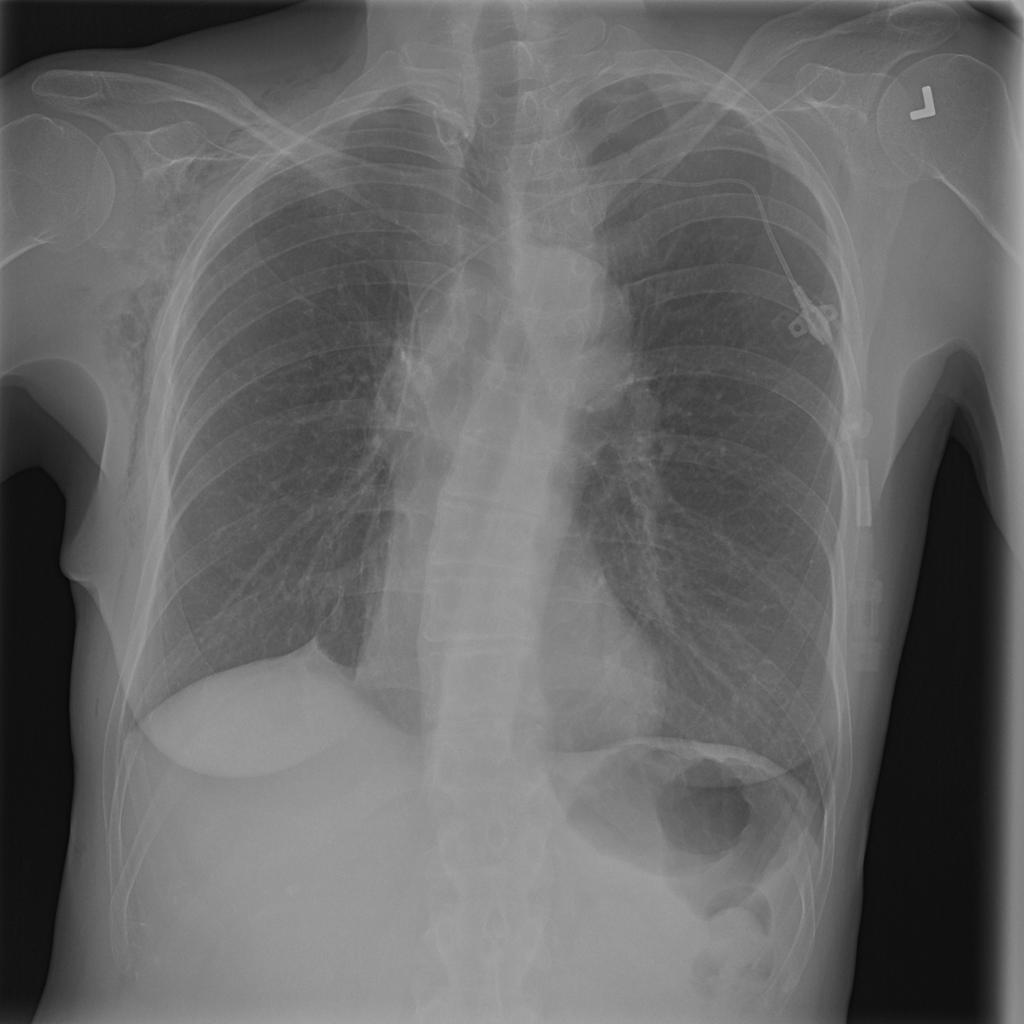

PAT-C255 · IMG-000Emphysema

PAT-C255 · IMG-000

PA